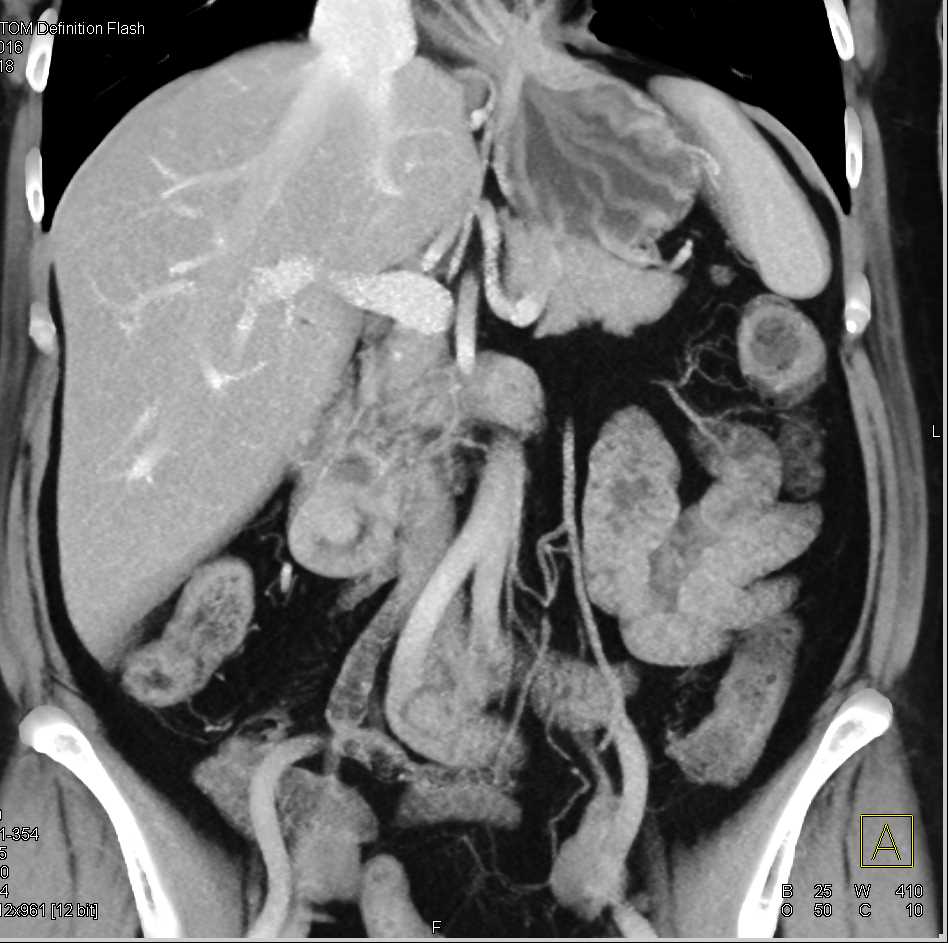

Small Bowel Obstruction (SBO) due to Midgut Volvulus